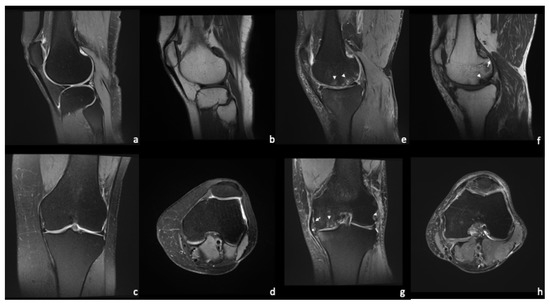

4. Magnetic Resonance Imaging—Common Findings

Figure 3. Standard protocol for knee evaluation. Healthy knee joint (ad) vs. severe OA of the medial compartment (eh) with BML (arrowheads), meniscal extrusion (star), and small osteophytes (arrows). The articular cartilage shows irregular thickness with some full thickness lesions (g).